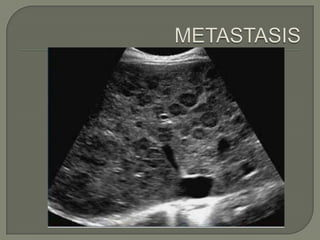

 Metástasis

   Más frecuente que CHC.

   Incidencia depende tipo de tumor y estadío del dx inicial.

   Ùnica o mùltiple

   Infiltración difusa o geográfica.